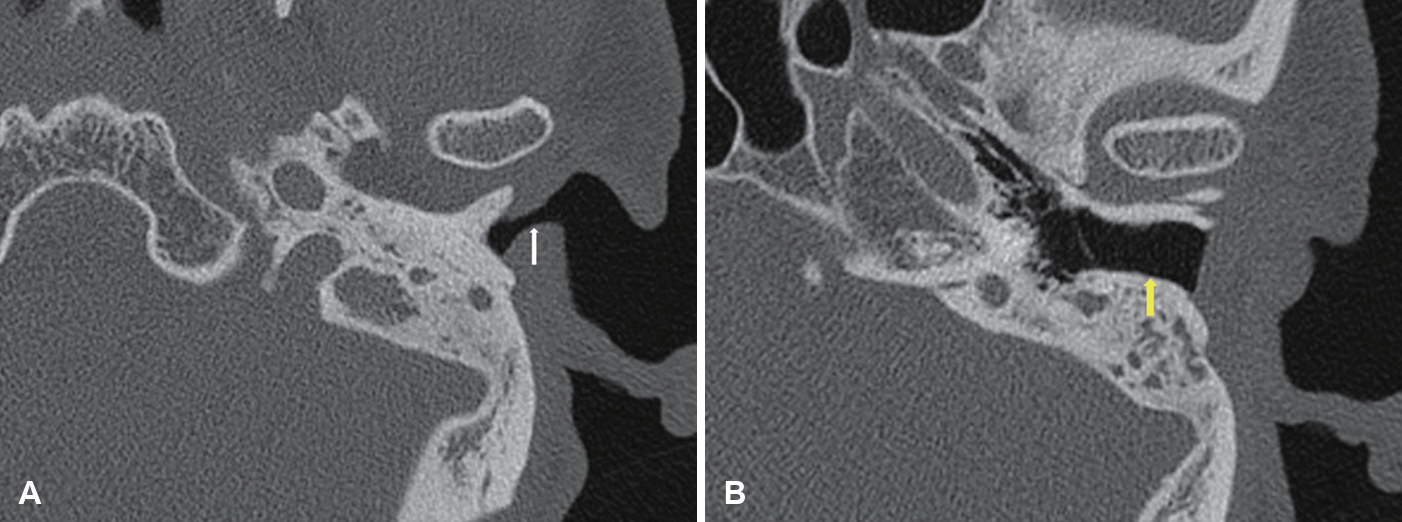

Preoperative temporal bone CT demonstrating a narrowed external meatus (left ear). The CT scan shows a markedly narrowed external meatus (A, white arrow) compared to the diameter of the external auditory canal (B, yellow arrow).